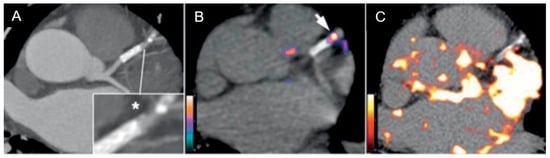

- Dweck, M.R.; Chow, M.W.; Joshi, N.V.; Williams, M.C.; Jones, C.; Fletcher, A.M.; Richardson, H.; White, A.; McKillop, G.; van Beek, E.J.; et al. Coronary arterial 18F-sodium fluoride uptake: A novel marker of plaque biology. J. Am. Coll. Cardiol. 2012, 59, 1539–1548. [Google Scholar] [CrossRef]

- Joshi, N.V.; Vesey, A.T.; Williams, M.C.; Shah, A.S.V.; A Calvert, P.; Craighead, F.H.M.; Yeoh, S.E.; Wallace, W.; Salter, D.; Fletcher, A.M.; et al. 18F-fluoride positron emission tomography for identification of ruptured and high-risk coronary atherosclerotic plaques: A prospective clinical trial. Lancet 2014, 383, 705–713. [Google Scholar] [CrossRef]

- Kitagawa, T.; Yamamoto, H.; Toshimitsu, S.; Sasaki, K.; Senoo, A.; Kubo, Y.; Tatsugami, F.; Awai, K.; Hirokawa, Y.; Kihara, Y. 18F-sodium fluoride positron emission tomography for molecular imaging of coronary atherosclerosis based on computed tomography analysis. Atherosclerosis 2017, 263, 385–392. [Google Scholar] [CrossRef] [PubMed]

- Tzolos, E.; Kwiecinski, J.; Lassen, M.L.; Cadet, S.; Adamson, P.D.; Moss, A.J.; Joshi, N.; Williams, M.C.; van Beek, E.J.R.; Dey, D.; et al. Observer repeatability and interscan reproducibility of 18F-sodium fluoride coronary microcalcification activity. J. Nucl. Cardiol. 2020, 29, 126–135. [Google Scholar] [CrossRef] [PubMed]